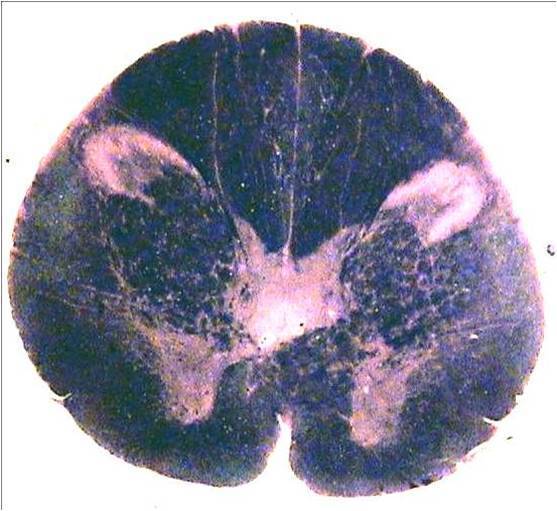

Question

Elige la alternativa correcta y arrástrala hasta la estructura marcada.

Image:

e4ae50bd-21b8-4e7e-b13e-cf9f8d7475a5 (image/jpeg)

Answer

leminisco trigenimal

lemnisco medial

formacion reticular

tracto espinotalamico

respecto a la imagen de la pregunta 10 , de la estructura marcada es correcto:

lleva información de la cara hacia el talamo.

lleva información de propiocepcion.

lleva información de termalgesia.

lleva información de la cara hacia la corteza cerebral.